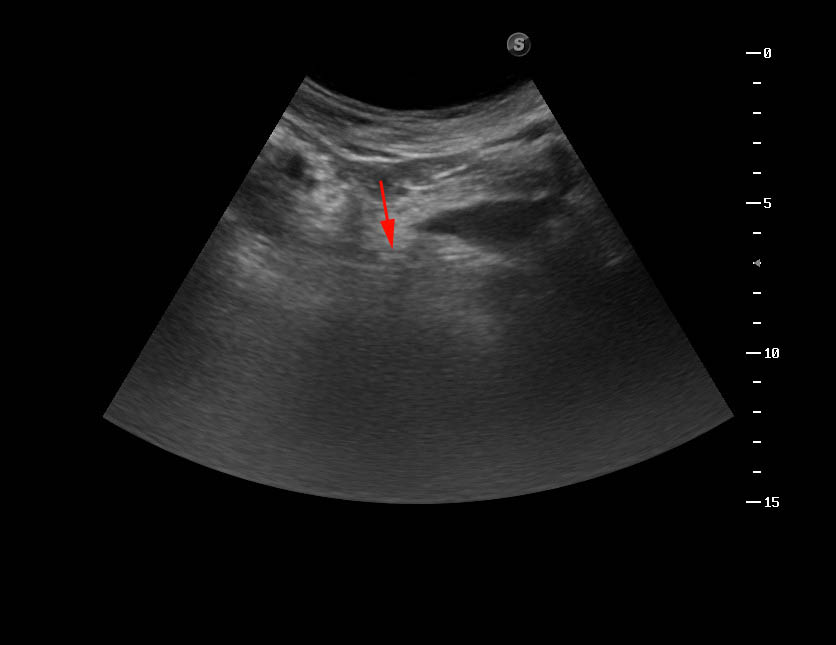

УЗИ: инспекция мочеточника. Sonographic inspection of an ureter. #3

Почки, мочеточники, мочевой пузырь, уретра. Простата и яички.